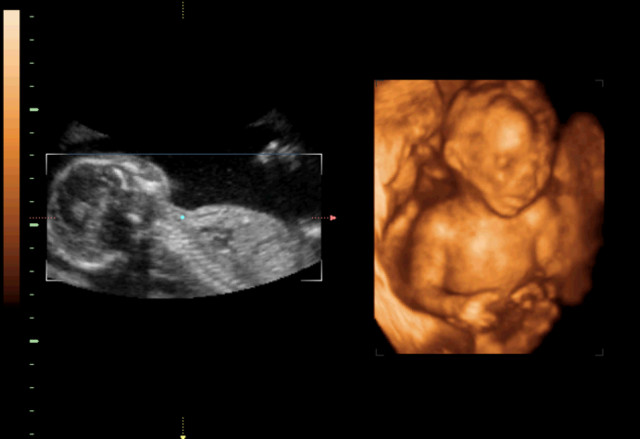

30岁的小孙就有唇裂,修补过的疤痕仍很分明。在最近一次三维B超显示,腹中的胎儿居然中度唇裂。她通知大夫,由于她诞生就有唇裂,小时老是被讪笑和厌弃。所有,无论怎样也要流掉腹中的宝宝,她不想让她的孩子再经历这样的经历。

大夫却通知小孙,现在已经孕21周,如果引产对身材损伤十分大,如果在次怀孕,不能包证就不会得唇腭裂,第二次仍会怀上唇腭裂宝宝的几率约为4%,假如怀过两次唇腭裂的宝宝,第三次怀上唇腭裂宝宝的几率会提升到14%。如今婴儿唇腭裂整形手艺,已经十分胜利,即使是重度的唇腭裂,仍是能够修补得简直看不出来了。倡议把孩子生上去,不要由于这点瑕疵,就将宝宝的性命闭幕。